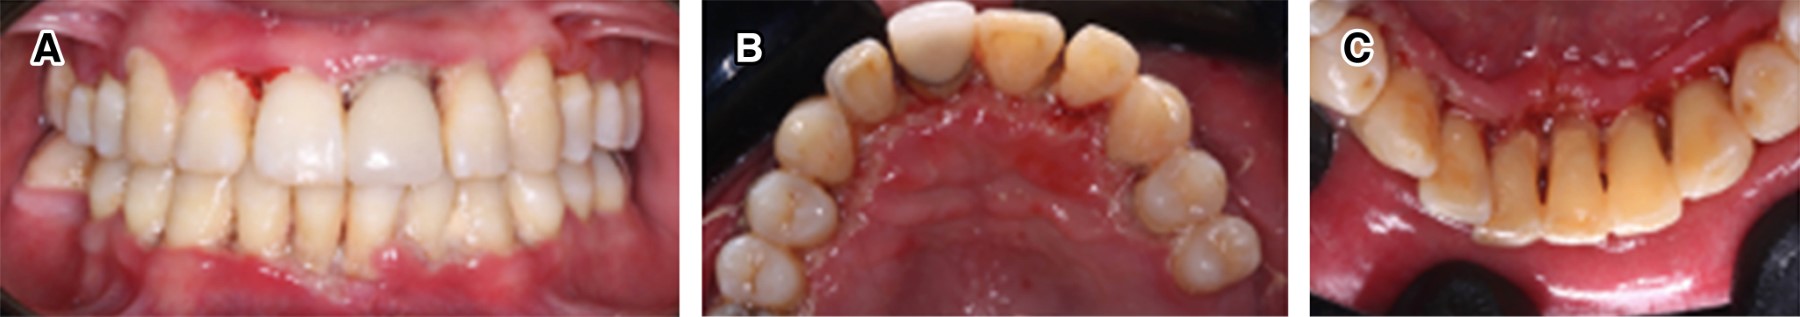

Figure 1